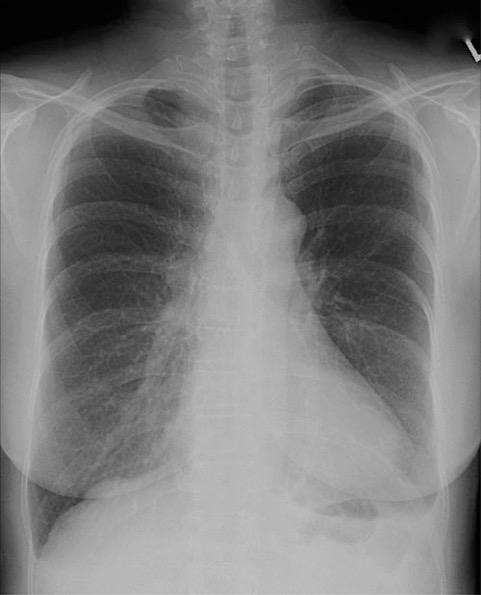

Which of the following criteria are used to evaluate a PA projection of the chest?

D 1, 2, and 3

-To evaluate sufficient inspiration and lung expansion, 10 posterior ribs should be visualized. The sternoclavicular joints should be symmetrical; any loss of symmetry indicates rotation. To visualize maximum lung area, the shoulders are rolled forward to move the scapulae laterally from the lung fields.